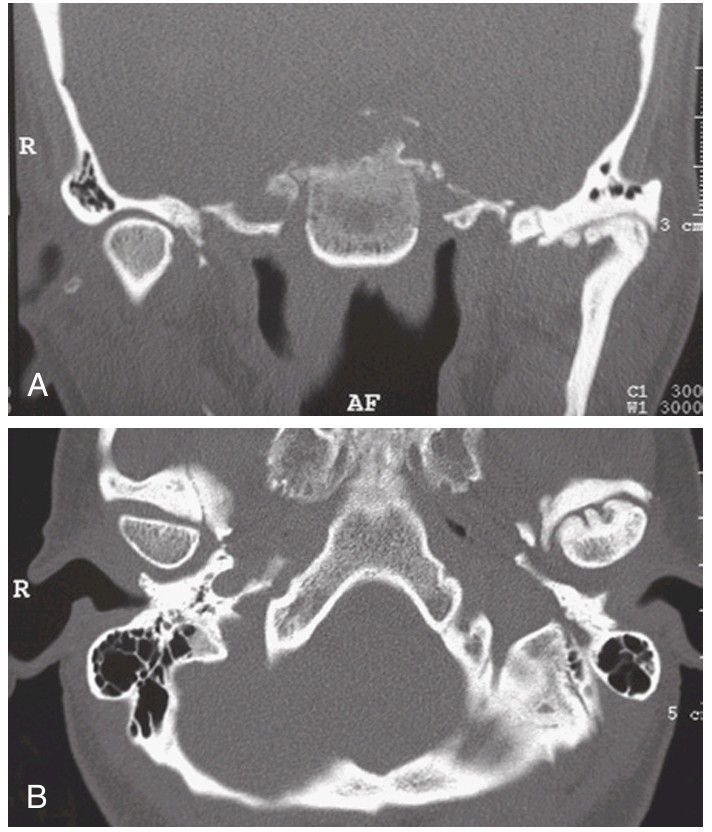

Computed tomography.

(A) Coronal image illustrates normal architecture of the right (R) condyle with alteration of the left condyle resulting from a history of trauma. (B) Axial view depicts the altered condylar anatomy referenced against the contralateral joint.